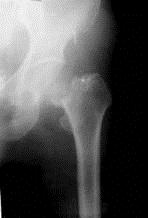

问题 病历摘要: 患者××,女性,70岁,不慎跌倒致伤左髋部后疼痛、活动障碍2天。查体:左下肢呈屈髋屈膝及外旋畸形,右下肢活动时左髋部疼痛,左足跟和大粗隆有叩击痛。 该患者以下处理哪些是正确的?

选项 A、行左全髋关节置换术 B、行多钉内固定+股骨颈植骨术 C、复位后行DHS内固定 D、行左人工股骨头置换术 E、复位后行三翼钉内固定 F、复位后行多钉内固定 G、皮肤牵引,保守治疗

答案 A

解析 A